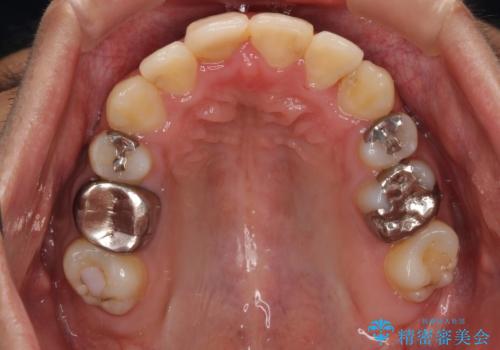

- 前歯のデコボコと八重歯、開咬を気にして来院された患者様です。

骨格的に下顎骨が上顎骨に対して後退位であったため、上顎の左右第一小臼歯を抜歯し、デコボコを改善するとともに開咬を改善していくこととしました。